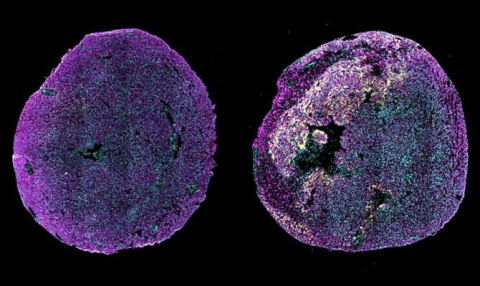

Desentrañando cómo se origina el cáncer infantil más frecuente